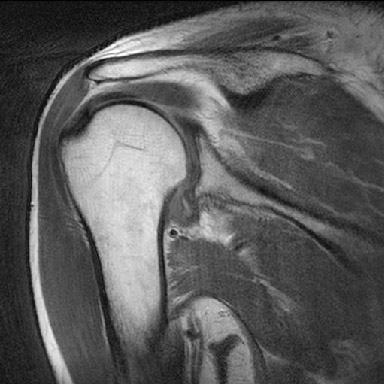

견관절낭염 환자의 방사선 영상